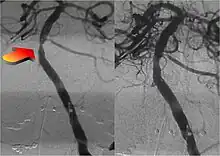

Endovascular repair of cerebral aneurysm